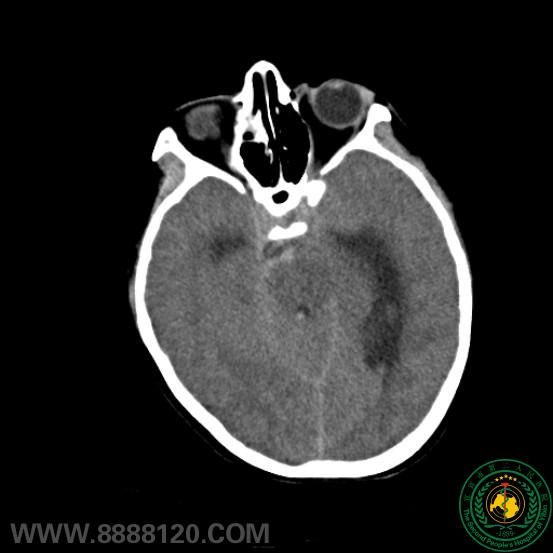

患儿11岁  以突发头痛伴意识障碍入院  头颅CT示蛛网膜下腔出血(桥前池为著),脑积水,脑室积血。